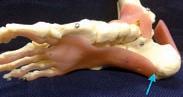

PAD, manifested as CLTI, the rate of MACEs and MALEs was 22.6% and 57.2% over 2.5 years, respectively.

“Roughly a fifth will have a cardiac event such as a heart attack in their lifetime and roughly two thirds of them will have an adverse lower limb event, which may mean amputation. In Australia, the cost is $1 billion a year – that’s 20,000 endovascular procedures a year, 5000 open operations for bypass surgery and 1800 legs amputated,” Dr Jansen said.

Compared to coronary artery disease (CAD) and cerebrovascular disease (CeVD), PAD is underappreciated, even though it affects over 230 million people worldwide and is associated with the highest morbidity and mortality rates globally.

Patients with symptomatic lowerextremity PAD generally have more extensive atherosclerosis than those with CAD or CeVD and, despite improved treatment options, the mortality rate in patients with PAD is substantially greater than in the general population – twice the rate in those with intermittent claudication [IC].

“Over time, it can progress to what we call chronic limb threatening ischemia, or CLTI, which is the most severe end of the spectrum where the limb is threatened. In that group of CLTI patients, their mortality is worse than many cancers and fivefold the general population rate,” Professor Jansen said.

Compared to CAD, patients with PAD also have a 1.5 to twofold greater risk for major adverse cardiovascular or limb events (MACEs or MALEs) and those risks increase alongside disease severity: in a contemporary series of Australian patients with greater-risk

“Similarly, revascularisation of CLTI limbs forms a large part of our work in vascular surgery now and what we spend the most time treating at Sir Charles Gairdner Hospital.”

PAD is increasing worldwide with a prevalence that grew >20% over the past decade, with even steeper increases expected for the next decade because of the ageing population and the increasing prevalences of diabetes and obesity – not to mention the rise of smoking in developing countries.

“The rapid increase in diabetes as an accelerant of PAD is bringing it into focus more and more,” Dr Jansen explained.

“There's a significant overlap between PAD and diabetes but diabetes is slightly different because it also has a predilection for smaller vessels and the microcirculation which is why we see retinopathy and nephropathy for example, but also diabetic foot with ulceration and the need for minor and major amputation.”